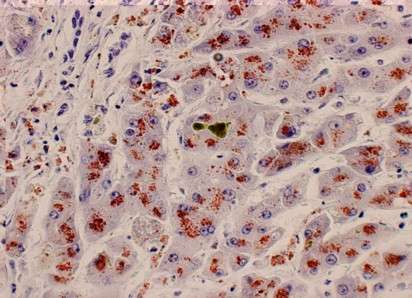

- Concentración elevada de cobre hepático:

- La acumulación de cobre en el tejido hepático es un hallazgo característico. Una concentración superior a 250 microgramos por gramo de tejido hepático seco se considera diagnóstica. Sin embargo, la distribución desigual del cobre en el hígado puede limitar la sensibilidad de este criterio, especialmente en etapas iniciales de la enfermedad.

- Biopsia hepática:

- Además de confirmar la acumulación de cobre, la biopsia hepática puede revelar características histológicas asociadas, como hepatitis aguda o crónica, esteatosis o cirrosis. Este procedimiento sigue siendo una herramienta crucial cuando las pruebas no invasivas no son concluyentes.